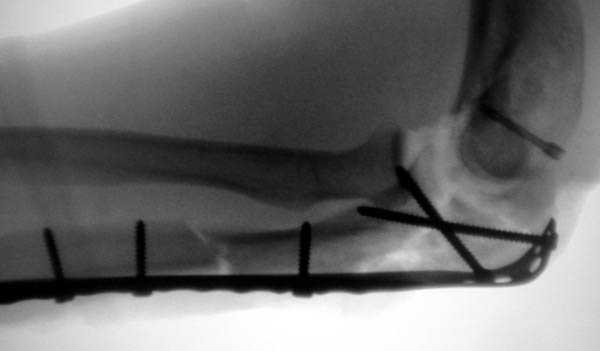

2 вариант

перелом локтевого отростка с переломом головки лучевой кости (использованы 2 мм шурупы)